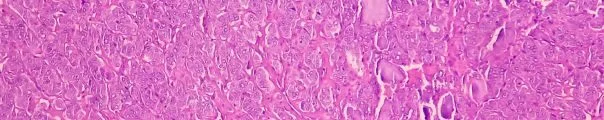

Uterine leiomyosarcoma (uLMS) is a rare and aggressive cancer of the uterus that often mimics benign fibroids, grows rapidly, and carries a poor prognosis. SPARC collaborated with the Briger Foundation for Oncology Research to conduct a comprehensive landscape analysis of uLMS and identify critical research gaps and strategic opportunities where philanthropic investment can accelerate scientific discovery, pave a path toward precision medicine, and ultimately enhance outcomes for patients.

Follicular lymphoma is a slow-growing, incurable form of non-Hodgkin’s lymphoma characterized by cycles of remission and relapse, with a subset of patients experiencing rapid progression and poorer outcomes. The Follicular Lymphoma Foundation engaged SPARC to advance research and accelerate treatment innovation by identifying strategic therapeutic funding opportunities and fostering collaborations that maximize philanthropic funding.